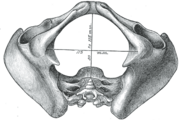

A distinction is made between the lesser or true pelvis inferior to the terminal line, and the greater or false pelvis above it. The pelvic inlet or superior pelvic aperture, which leads into the lesser pelvis, is bordered by the promontory, the arcuate line of ilium, the iliopubic eminence, the pecten of the pubis, and the upper part of the pubic symphysis. The pelvic outlet or inferior pelvic aperture is the region between the subpubic angle or pubic arch, the ischial tuberosities and the coccyx. [2]

Alternatively, the pelvis is divided into three planes: the inlet, midplane, and outlet.[3]

Diameters of pelvic inlet